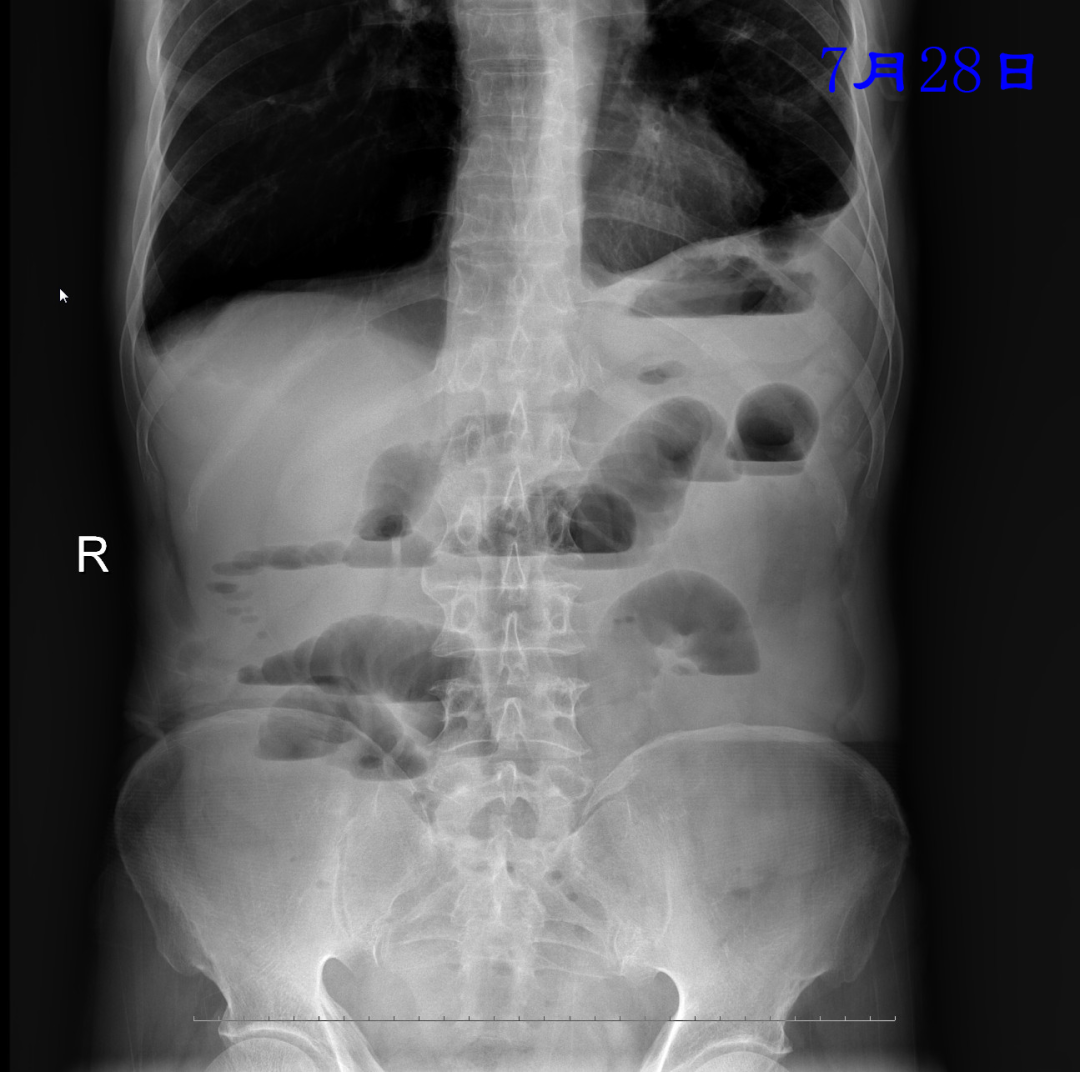

病例:患者男性,74岁,因“腹痛、腹胀伴呕吐、肛门停止排气排便20小时”于2021年7月24日入住我院普外科。患者1月前因回肠穿孔于我院普外科手术治疗,入院后明确诊断为术后粘连性小肠梗阻,经胃管引流等保守治疗无好转。因患者有严重心肺疾患,再次手术风险较大,并且术后再发粘连性肠梗阻的可能性也很大。经过与患者家属沟通后,最后决定采用胃镜引导下置入经鼻插入型肠梗阻导管技术来治疗肠梗阻。由我院消化内科副主任医师杨开余完成操作,耗时大约40分钟,患者术后第5天开始排气排便,腹痛、腹胀症状迅速消失,术后第7天拔除肠梗阻导管,恢复饮食。拔管至今已10天,患者已出院。随访患者无腹痛、腹胀,排便正常。

良好的引流是治疗肠梗阻的基本措施,低位小肠梗阻置入胃管引流常难以奏效,以往大多需要再次手术,而再次手术后粘连的几率高达70%。经鼻插入型肠梗阻导管就是将一根3米多长,内有四个腔道的管道置入十二指肠后,在重力和肠道蠕动的作用下,导管先端部将自动向前运动,直至到达梗阻部位。在导管到达梗阻部位后,可进行双对比造影检查了解狭窄病因,也可以对狭窄处进行扩张,还可以作为支架起到肠排列的治疗效果。肠梗阻导管治疗小肠梗阻属于微创型手术,具有痛苦小、疗效好、费用低、预防再次粘连等优点。